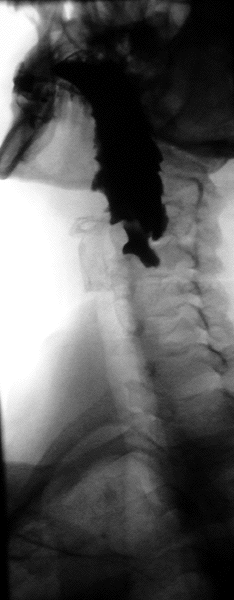

Die Symptomatik variiert in Abhängigkeit vom Stadium des Divertikels. Nicht alle Divertikel sind symptomatisch. In den frühen Stadien (Brombart 1 und 2) kommt es noch nicht zu einer Retention von Speisen im Divertikel, da sich das Divertikel nur temporär während des Schluckaktes ausstülpt und im Intervall wieder komplett in der Pharynxhinterwand verstreicht. Im Vordergrund steht häufig eine Dysphagie, meist in Form eines Fremdkörpergefühls (Globusgefühl). Man spricht von Pouches („Taschen“) im Gegensatz zu den permanent nachweisbaren Divertikeln in den höheren Stadien (Brombart 3 und 4). Hier kann bei Speiseresten im Divertikel zusätzlich ein starker Mundgeruch entstehen. Es kommt zur Regurgitation von ungesäuertem Essen (diagnostisch wegweisend: Das Essen war nicht im Magen; im Gegensatz zum Reflux). Husten kann ein Hinweis darauf sein, dass Divertikelinhalt (Nahrungsreste) in die Luftröhre übertritt, es kann zu einer Aspirationspneumonie (Lungenentzündung) kommen. Zudem führen die Schluckbeschwerden nicht selten bei älteren Menschen zu einer Gewichtsabnahme.

Die Diagnostik erfolgt bei entsprechenden Symptomen mit der Endoskopie und Röntgenaufnahmen mit Kontrastmittel. Sobald ein Patient Schluckstörungen bemerkt, sollte er sich in fachärztliche Betreuung begeben, denn diverse Erkrankungen der Speiseröhre können diese Beschwerden hervorrufen. Danach sollte eine genaue Inspektion von Mund und Rachen des Patienten erfolgen und der Hals nach vergrößerten Lymphknoten oder Weichteilveränderungen abgetastet werden. Je nach Verdachtsdiagnose wird eine Spiegelung der Speiseröhre durchgeführt und gleichzeitig im Bereich auffälliger Schleimhautbereiche eine Gewebeprobe entnommen. Ergänzend, vor allem bei Divertikeln, wird eine Röntgenuntersuchung der Speiseröhre mit flüssigem Kontrastmittel durchgeführt, die auch Bewegungsstörungen der Speiseröhrenwand zeigen kann. Handelt es sich bei der Erkrankung um einen Tumor, ist es unter Umständen notwendig, eine zusätzliche CT- oder MRI-Untersuchung durchzuführen, um seine Ausdehnung und Lage im Brustkorb zu sehen. Unter Umständen ist auch eine Voruntersuchung durch einen Hals-Nasen-Ohren-Arzt notwendig, der die Funktionsfähigkeit eines wichtigen Nervs im Bereich des Kehlkopfes überprüfen muss. Je nach Vorerkrankungen und Alter des Patienten werden auch Ultraschalluntersuchungen am Herzen sowie eine Lungenfunktionsprüfung durchgeführt. Bei einem Zenker-Divertikel ist die Indikation zur Operation gegeben, völlig unabhängig davon, wie stark die Beschwerden des Patienten sind, denn die Komplikationsrate ist gering.